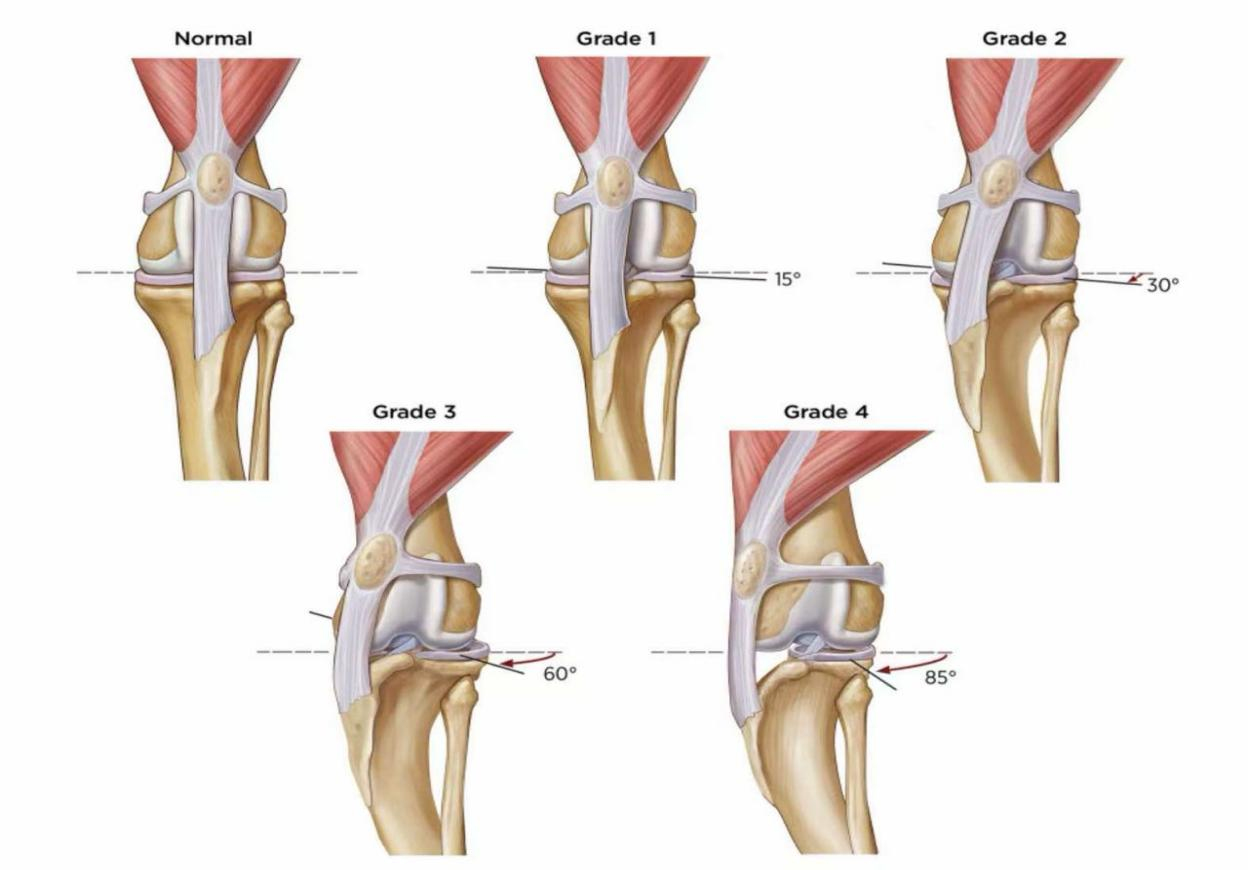

髌骨脱位是一种常见疾病,尤其在小型犬中更为多发。按严重程度分为1-4级。Coco左侧已达最严重的4级,意味着髌骨完全脱位且无法自行复位,伴随骨骼畸形和关节磨损;右侧为3级,髌骨频繁脱位但可手动复位。若不及时手术,Coco将面临关节炎加重、肌肉萎缩甚至有可能终身残疾的风险。